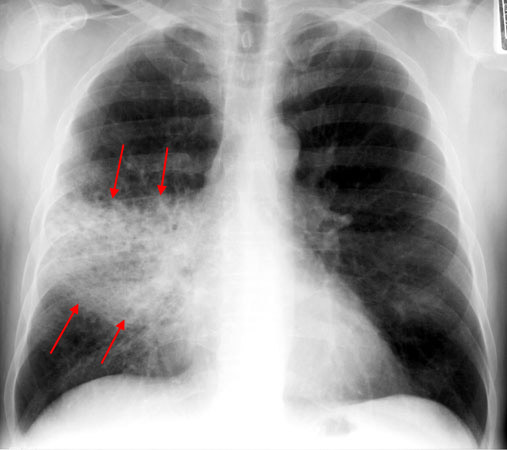

Other findings can take much longer (Fig).